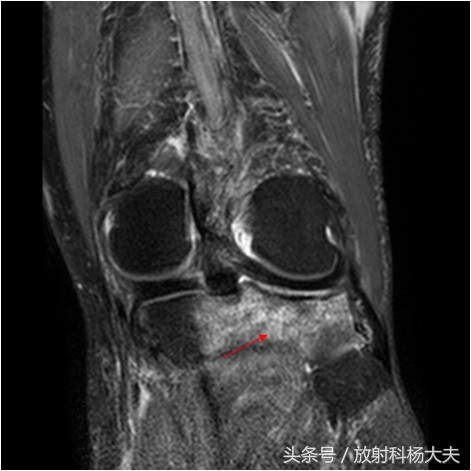

扭伤膝关节,拍片未见异常,做了核磁发现骨挫伤

骨挫伤是外伤所致的骨髓出血、水肿和骨小梁的微骨折, 常见原因是关节囊及韧带的牵拉力、垂直挤压、直接*力暴**、应力损伤、剪切*力暴**等。 只是因为创伤导致的损伤未能引起明显的骨折线,因此在X线平片上看不到骨折而已。骨挫伤还有很多其他名称,比如骨小梁骨折、微骨折等。其基础,不单单是水肿,还有出血和微骨折,由于核磁对水的变化很敏感,因此做核磁是最好的显示骨挫伤的办法。

骨挫伤的情势各异,骨小梁出血灶呈点状、斑片状或散在分布于骨质中。直接*力暴**所致骨挫伤往往造成着力处骨小梁断裂,继而发生广泛渗出,可合并肌腱、关节囊、韧带损伤。撕脱性*力暴**所致骨挫伤可导致肌腱或韧带附着点骨质水肿、出血。应力损伤性骨挫伤特点为:应力作用的方向与骨小梁断裂的方向垂直。剪切损伤特点为骨挫伤的出血点和水肿灶呈斜行,且边界清晰。